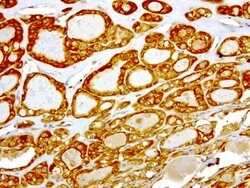

NME1 Mouse anti-Canine, Human, Rat, Clone: UMAB94, liquid, UltraMAB™

NME1 was identified because of its reduced mRNA transcript levels in highly metastatic cells. Nucleoside diphosphate kinase (NDK) exists as a hexamer composed of ′A′ (encoded by this gene) and ′B′ (encoded by NME2) isoforms. Mutations in the gene have been identified in aggressive neuroblastomas. Two transcript variants encoding different isoforms have been found for this gene. Co-transcription of this gene and the neighboring downstream gene (NME2) generates naturally-occurring transcripts (NME1-NME2), which encodes a fusion protein comprised of sequence sharing identity with each individual gene product.Specifications

| Immunocytochemistry, Immunofluorescence, Immunohistochemistry (Paraffin) | |